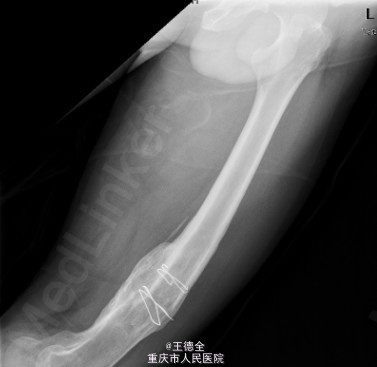

患者男,40岁,因“左股骨下段骨折术后4+年,左膝反复肿痛2年余”入院;自诉于4年前不慎被石块砸伤左大腿,伤后即觉左大腿疼痛,流血,左下肢活动障碍,患者伤后即到当地医院就诊,诊断为:"左股骨下段开放性骨折",予骨折切开复位内固定术,术后3个月下地行走,术后内固定螺钉松动、脱落,近两年来出现左膝关节肿胀、疼痛,活动时肿胀、疼痛症状加重,无畏寒发热、肢端麻木等,患者病后曾到当地医院就诊,予服药治疗后症状无明显好转,为进一步诊治遂来我院就诊,门诊拟"左膝骨性关节炎"收住我科,病程中,患者一般情况尚可,睡眠、饮食可,大小便正常,体重无明显改变。目前积极完善术前检查,拟做关节镜下关节清理术+左膝腘窝囊肿切除手术治疗。